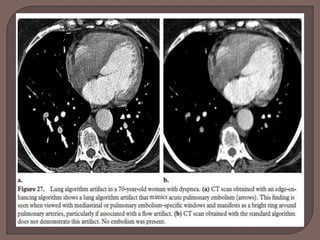

 The lung algorithm

• A high-spatial-frequency reconstruction convolution kernel

• Used to improve the quality of images of the pulmonary vessels,

bronchi, and interstitium.

 This algorithm can create image artifacts that appear similar

to pulmonary emboli.

 However, these artifacts can be removed with a standard

algorithm